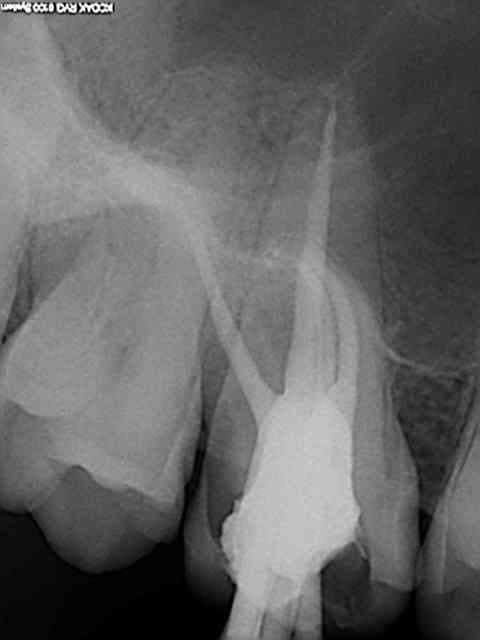

J'ai fais un cas, molaire, ça va bien.

http://www.eugenol.com/sujets/391302-reciproc-one-file-endo?page=14#post_593083